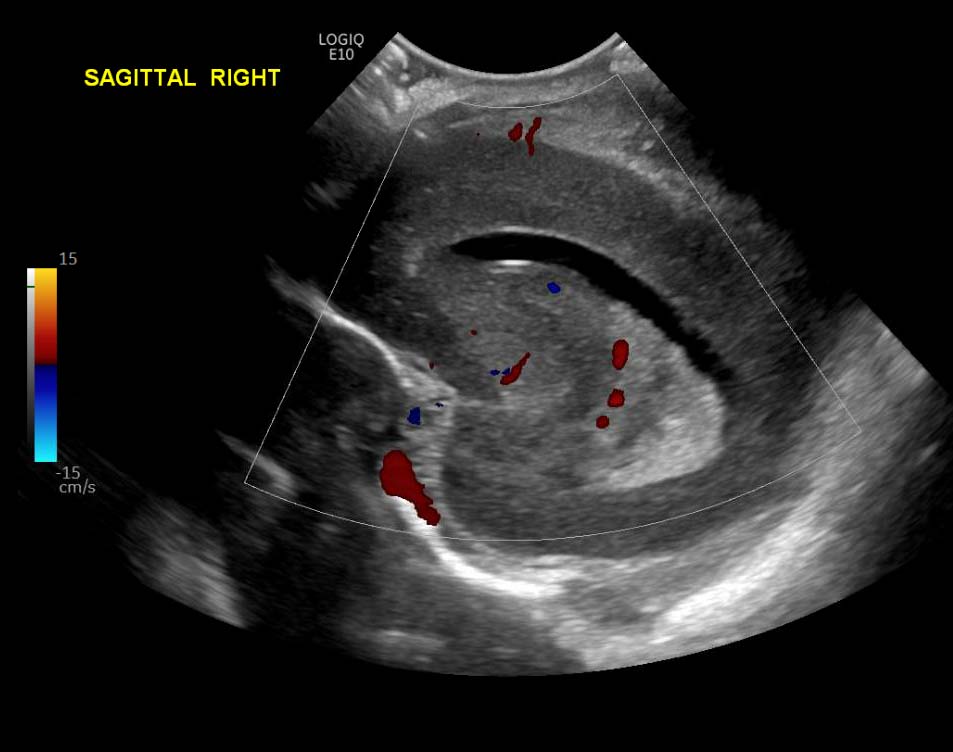

Age: 4 days (born at 24 weeks)

Sex: Male

Indication: Evaluate for germinal matrix hemorrhage

Grade 2 germinal matrix hemorrhage

Sample ReportLeft germinal matrix hemorrhage involving the caudothalamic groove and layering in the occipital horn of the left lateral ventricle without hydrocephalus (grade 2).

No abnormal brain parenchymal echogenicity or extra-axial collections.

Premature sulcation pattern.